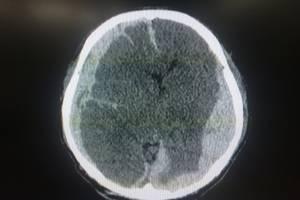

How to File a Personal Injury Claim After a Traumatic Brain Injury

Navigating life after experiencing a traumatic brain injury (TBI) can be both frightening and frustrating. You may be left wondering how to pay for treatment or rehabilitation and where you can find help filing a personal injury claim. Experiencing a TBI could significantly impact your, or a loved one’s, life, and it is important to reach out to a skilled attorney to help you determine if you are entitled to monetary compensation.

Car accidents, a slip-and-fall accident or an act of violence can all lead to a TBI. Due to the severity of this type of brain or spinal cord injury, it is critical that those affected look for dangerous complications that can occur. Symptoms to watch out for include: